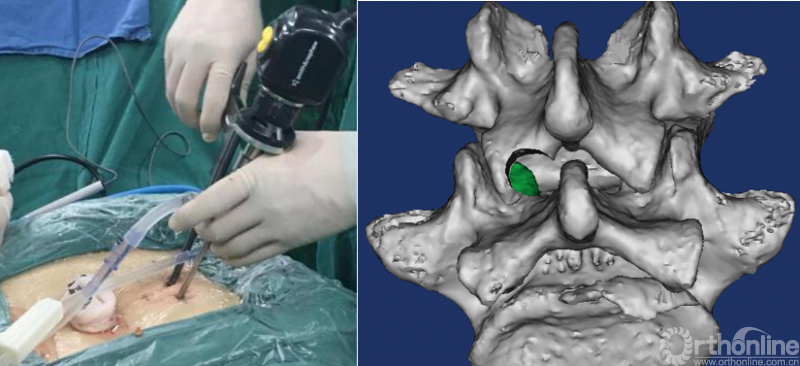

PE-PLIF技术十步法

详细步骤:一定、二辨、三凿、四分、五咬、六切、七旋、八铰、九填、十置

第一步“定”:X线定位在上位椎体下关节突下三分之一部;

第二步“辨”:镜下辨别下关节突关节囊;

第三步“凿”:凿除部分下关节突,显露上关节突及黄韧带;

第四步“分”:分离上关节突及黄韧带;

第五步“咬”:咬除部分上关节突,显露椎间盘及神经根;

第六步“切”:切除椎间盘;

第七步“旋”:旋转舌形套管保护神经根;

第八步“铰”:盲视下可撑开铰刀置入,撑开并处理上下终板;

第九步“填”;椎间隙填塞植骨;

第十步“置”:置入融合器、经皮钉。